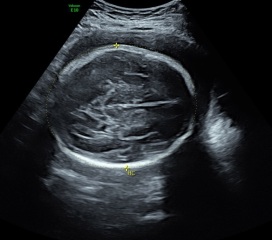

Can anyone see any fluid on my babies brain? I went for a private 4D ultrasound and they did a growth scan too, they said my baby had a slightly bigger head than average (98th percentile!!!!) and I've been googling..... she didn't mention any abnormalities.